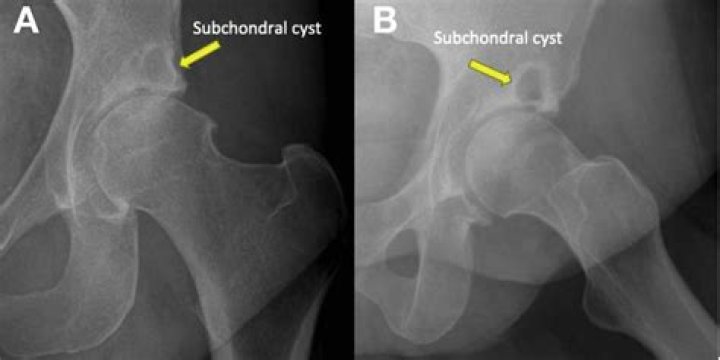

What is a subchondral cyst in the hip?

A subchondral cyst is a fluid-filled space inside a joint that extends from one of the bones that forms the joint. This type of bone cyst is caused by osteoarthritis. It may require aspiration (drawing the fluid out), but the arthritis condition usually must also be addressed to prevent further cyst formation.